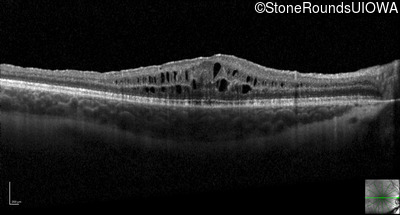

Optical Coherence Tomography - Right - 20/40 -2

Exemplar / OCT Stack